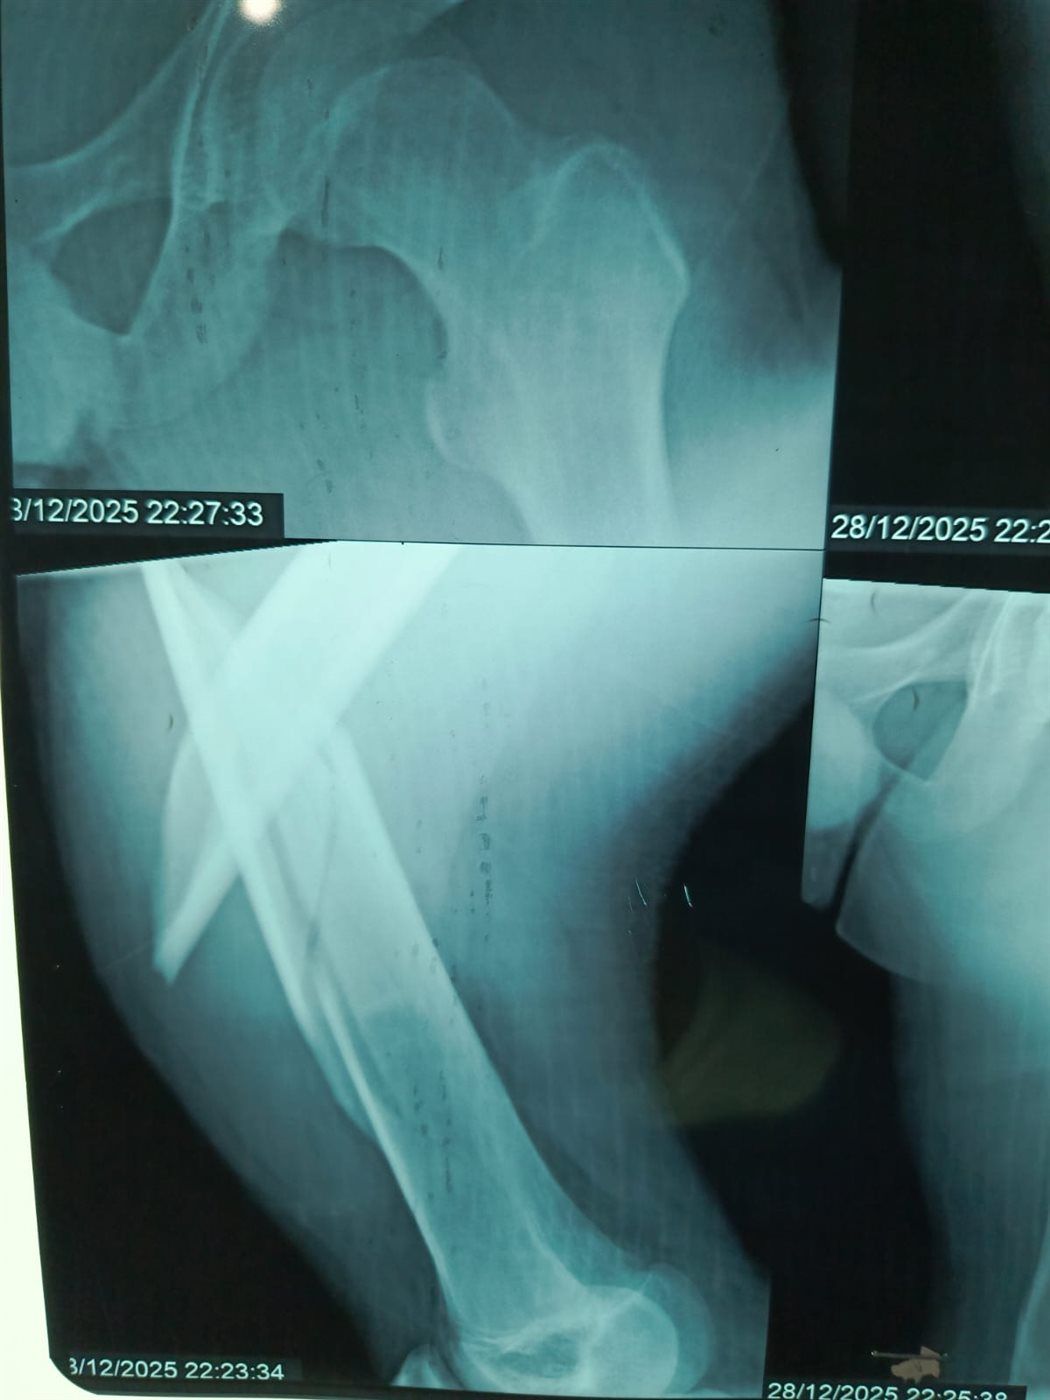

نجح الفريق الطبي بقسم الطوارئ والعمليات بمستشفى مغاغة العام بمحافظة المنيا، في إنقاذ شاب يبلغ من العمر 16 عامًا، تعرض لحادث مروري مروع أسفر عن كسر مفتت متعدد المواضع بعظمة الفخذ الأيسر، وذلك من خلال إجراء جراحة متقدمة باستخدام تقنية المسمار النخاعي التشابكي في زمن قياسي.

وفور وصول المصاب إلى قسم الطوارئ، جرى التعامل الفوري معه، وتم اتخاذ القرار الطبي العاجل بإجراء جراحة المسمار النخاعي التشابكي دون فتح موضع الكسر، بما يتوافق مع أحدث البروتوكولات الطبية العالمية. واستغرقت العملية نحو ساعتين ونصف فقط، غادر بعدها المريض غرفة العمليات في حالة مستقرة.

وتميزت الجراحة بعدة مزايا، من بينها: جروح جراحية محدودة للغاية، وتقليل فرص النزيف والعدوى إلى أدنى حد، وتسريع معدلات التئام العظام مقارنة بالطرق التقليدية.